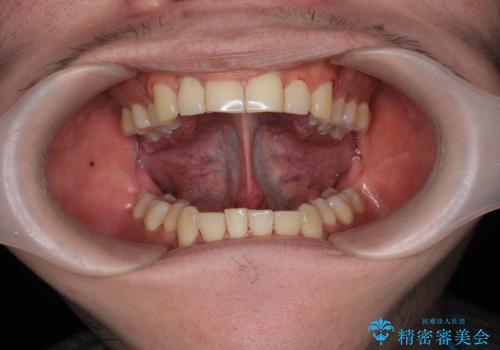

- 長年、指摘され悩みの種であった滑舌の改善を希望され来院されました。

舌の動きを制限してしまう下部のヒダが長い状態を改善する、舌小帯の形成を即日で行い滑舌の改善を計画します。